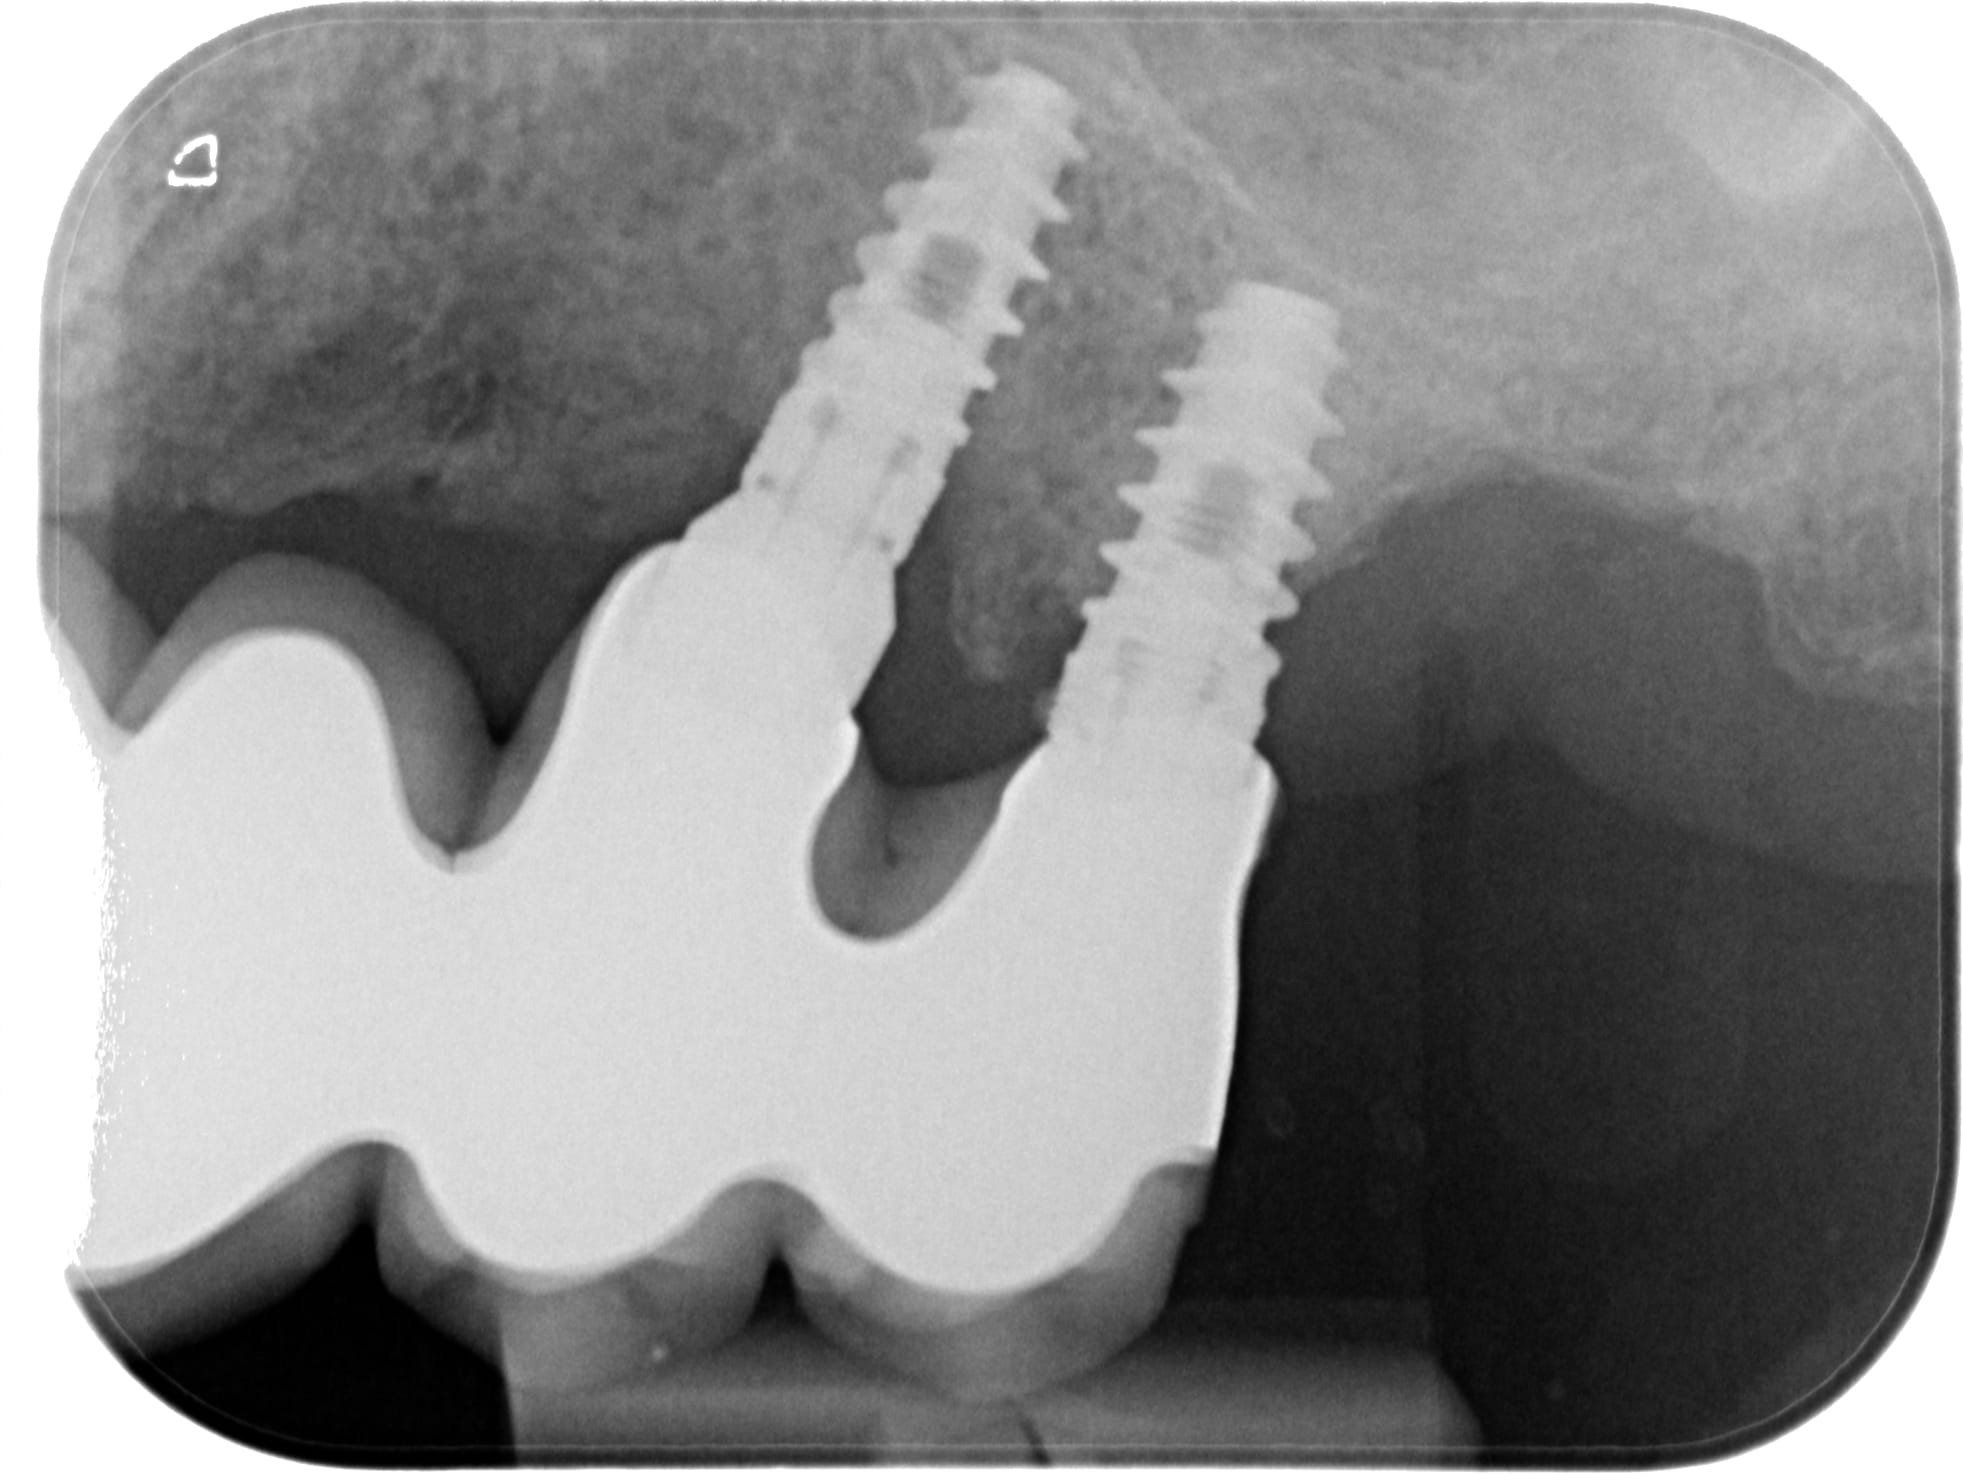

bonjour, j'ai besoin d'identifier les implants en 24 25 21 et 11. J'ai l'impression que c'est les mêmes mais le patient a un doute pour 11 qui n'a pas été posé en même temps (c'est l'implant qui n'a plus sa prothèse...). Merci d'avance!

à mon avis du AB dental

https://osseosource.com/i5-narrow-platform-3-75-/p-40.html